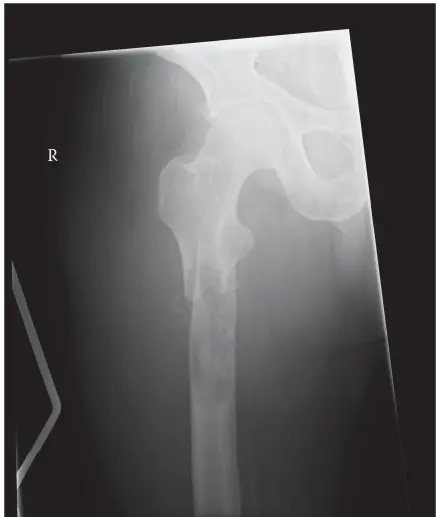

تشمل المواقع الشائعة للكسور المرضية: الجزء العلوي من عظم الفخذ، عظم العضد، العمود الفقري، والحوض. هذه المناطق غالبًا ما تكون عرضة لإجهاد ميكانيكي عالٍ وغنية بالأوعية الدموية، مما يجعلها بيئة مناسبة لاستقرار الخلايا السرطانية.

يُعد حجم وموقع الآفة داخل العظم من العوامل البيوميكانيكية الحاسمة. فإذا كانت الآفة تُصيب أكثر من 50% من محيط أو قطر قشرة العظم، خاصة في المناطق التي تتحمل الوزن، فهذا يُعد مؤشرًا قويًا على احتمالية حدوث كسر وشيك. كما أن الآفات في مناطق تركيز الإجهاد العالي، مثل منطقة تحت المدور في عظم الفخذ، والمنطقة بين المدورين، ومناطق التقاء الجسم بالمشاش في العظام الطويلة، تكون أكثر عرضة للكسور. يُعرف هذا المفهوم بـ "مُركّز الإجهاد" (Stress Riser)، حيث يُركز أي عيب موضعي القوى الميكانيكية، مما يزيد من خطر الكسر.